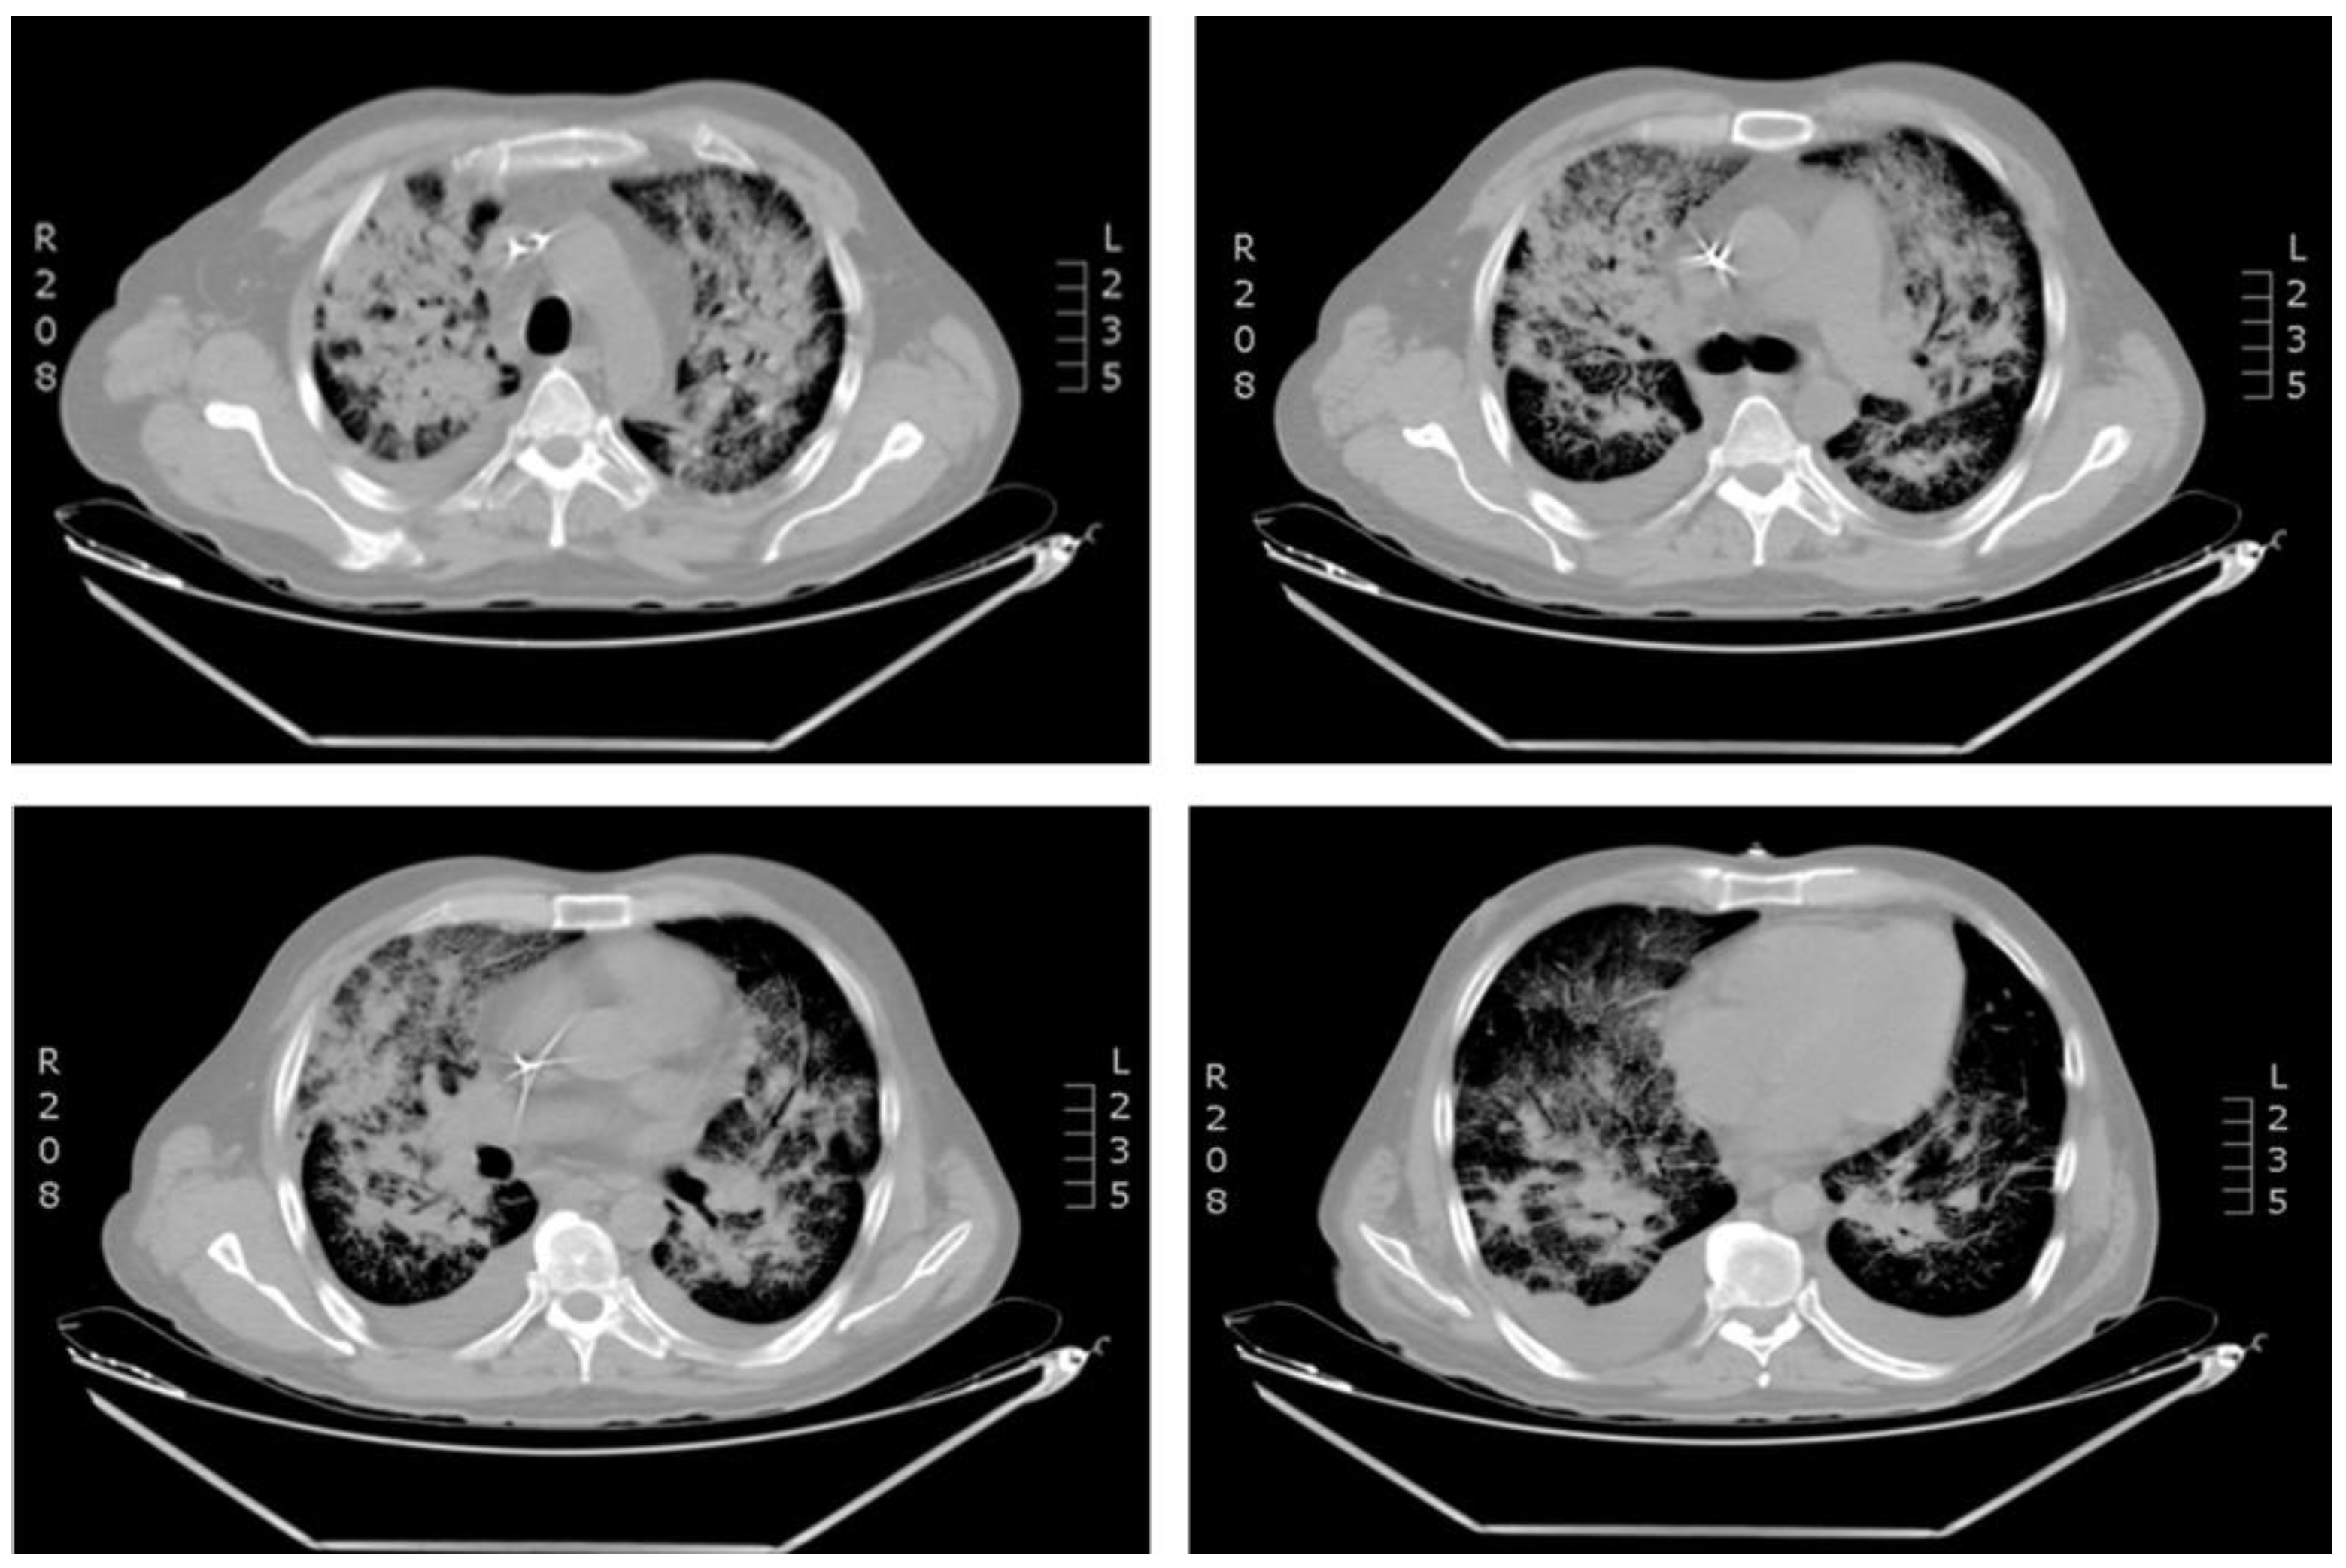

Figure 2.

Computed tomography (CT) scan of the chest revealing bilateral bronchopneumonia.

A 44-year-old Colombian man was admitted in a third level Clinic in Cali, Colombia at the end of February 2021 (rainy season). The patient had been diagnosed with acute lymphoblastic leukemia (ALL) two years previously, with history of two relapses. He referred five days of fever with no apparent cause. He had been treated with blinatumomab as a bridging therapy to stem cell transplant (SCT) and had finished the first month of treatment with blinatumomab ten days previously. Physical examination showed generalized paleness with normal vitals. At the time of admission, the patient was conscious and did not present urinary or respiratory symptoms. Pancytopenia was observed (Table 1). Blood transfusion of irradiated red blood cells and platelets was indicated; however, the pancytopenia did not improve, and other blood transfusions were required. Blood cultures were obtained and treatment with meropenem was initiated due to febrile neutropenia. Twenty-four hours after admission, the patient began to present respiratory symptoms, oxygen desaturation up to 60%, occasional cough, tachycardia, and hypotension. Treatment with vancomycin, amikacin and fluconazole was started. Chest X-ray showed increase in cotton wool opacities with commitment of all quadrants associated with bilateral broncho-pneumonic infiltrate in the consolidation process (Figure 1). Treatment for influenza virus (oseltamivir), Pneumocystis jirovecii (trimethoprim/sulfamethoxazole) and atypical bacterial infection (iv clarithromycin) was indicated, and COVID-19 was suspected. PCR and antigen detection in nasopharyngeal aspirate for SARS-CoV-2 were negative. Multiplex molecular detection of microorganisms (FilmArray, Biofire, USA) was requested. The patient continued presenting a rapid deterioration of his general condition with worsening of the respiratory pattern, desaturation, and severe hypoxemia, requiring non-invasive mechanical ventilation (the patient refused intubation). A CT scan of the lungs revealed severe bilateral bronchopneumonia, inflammatory hilar ganglia, and minor pleural effusion (Figure 2). Microbiological tests for bacteria, fungi, and mycobacteria were negative, but FilmArray was positive for coronavirus HCoV-NL63.There was no obvious contact with other people infected with HCoV-NL63. There is no specific treatment for this virus infection, thus supportive treatment was continued. Owing to the treatment with blinatumomab, secondary antibody deficiency was suspected, and humoral immune response was evaluated. Protein electrophoresis and serum immunoglobulins(IgG, IgA and IgM) levels revealed severe hypogammaglobulinemia (Table 1). Replacement therapy with intravenous immunoglobulins (IVIG) at a dose of 400 mg/kg (every 28 days) was indicated. Interestingly, the patient improved oxygenation diminishing supplementary oxygen requirement after only 24 hours from IVIG administration. The clinical evolution was adequate and the respiratory syndrome improved after 72 hours from IVIG administration (second molecular testing was not available). Treatment with blinatumomab was restarted. After the second dose of IVIG, his general health condition was good, and the patient was discharged. Currently the patient shows a good engraftment after 6 months from stem cell transplant with matched sibling donor, but he is still requiring IVIG due to hypogammaglobulinemia persistence (data not shown).